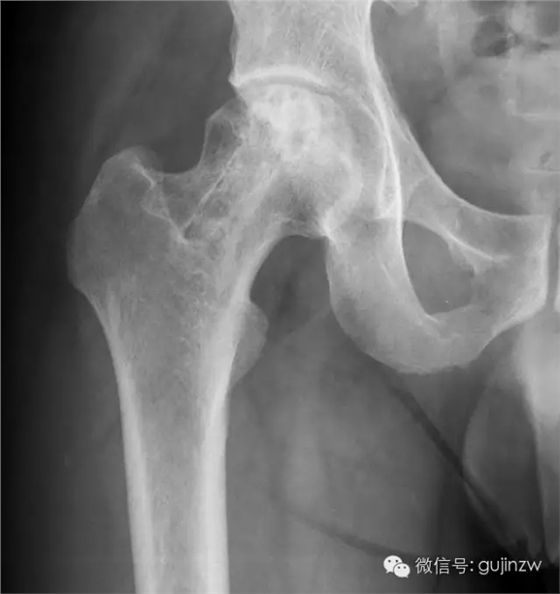

4、骨阻擋:髖關節(jié)脫位髖臼加蓋